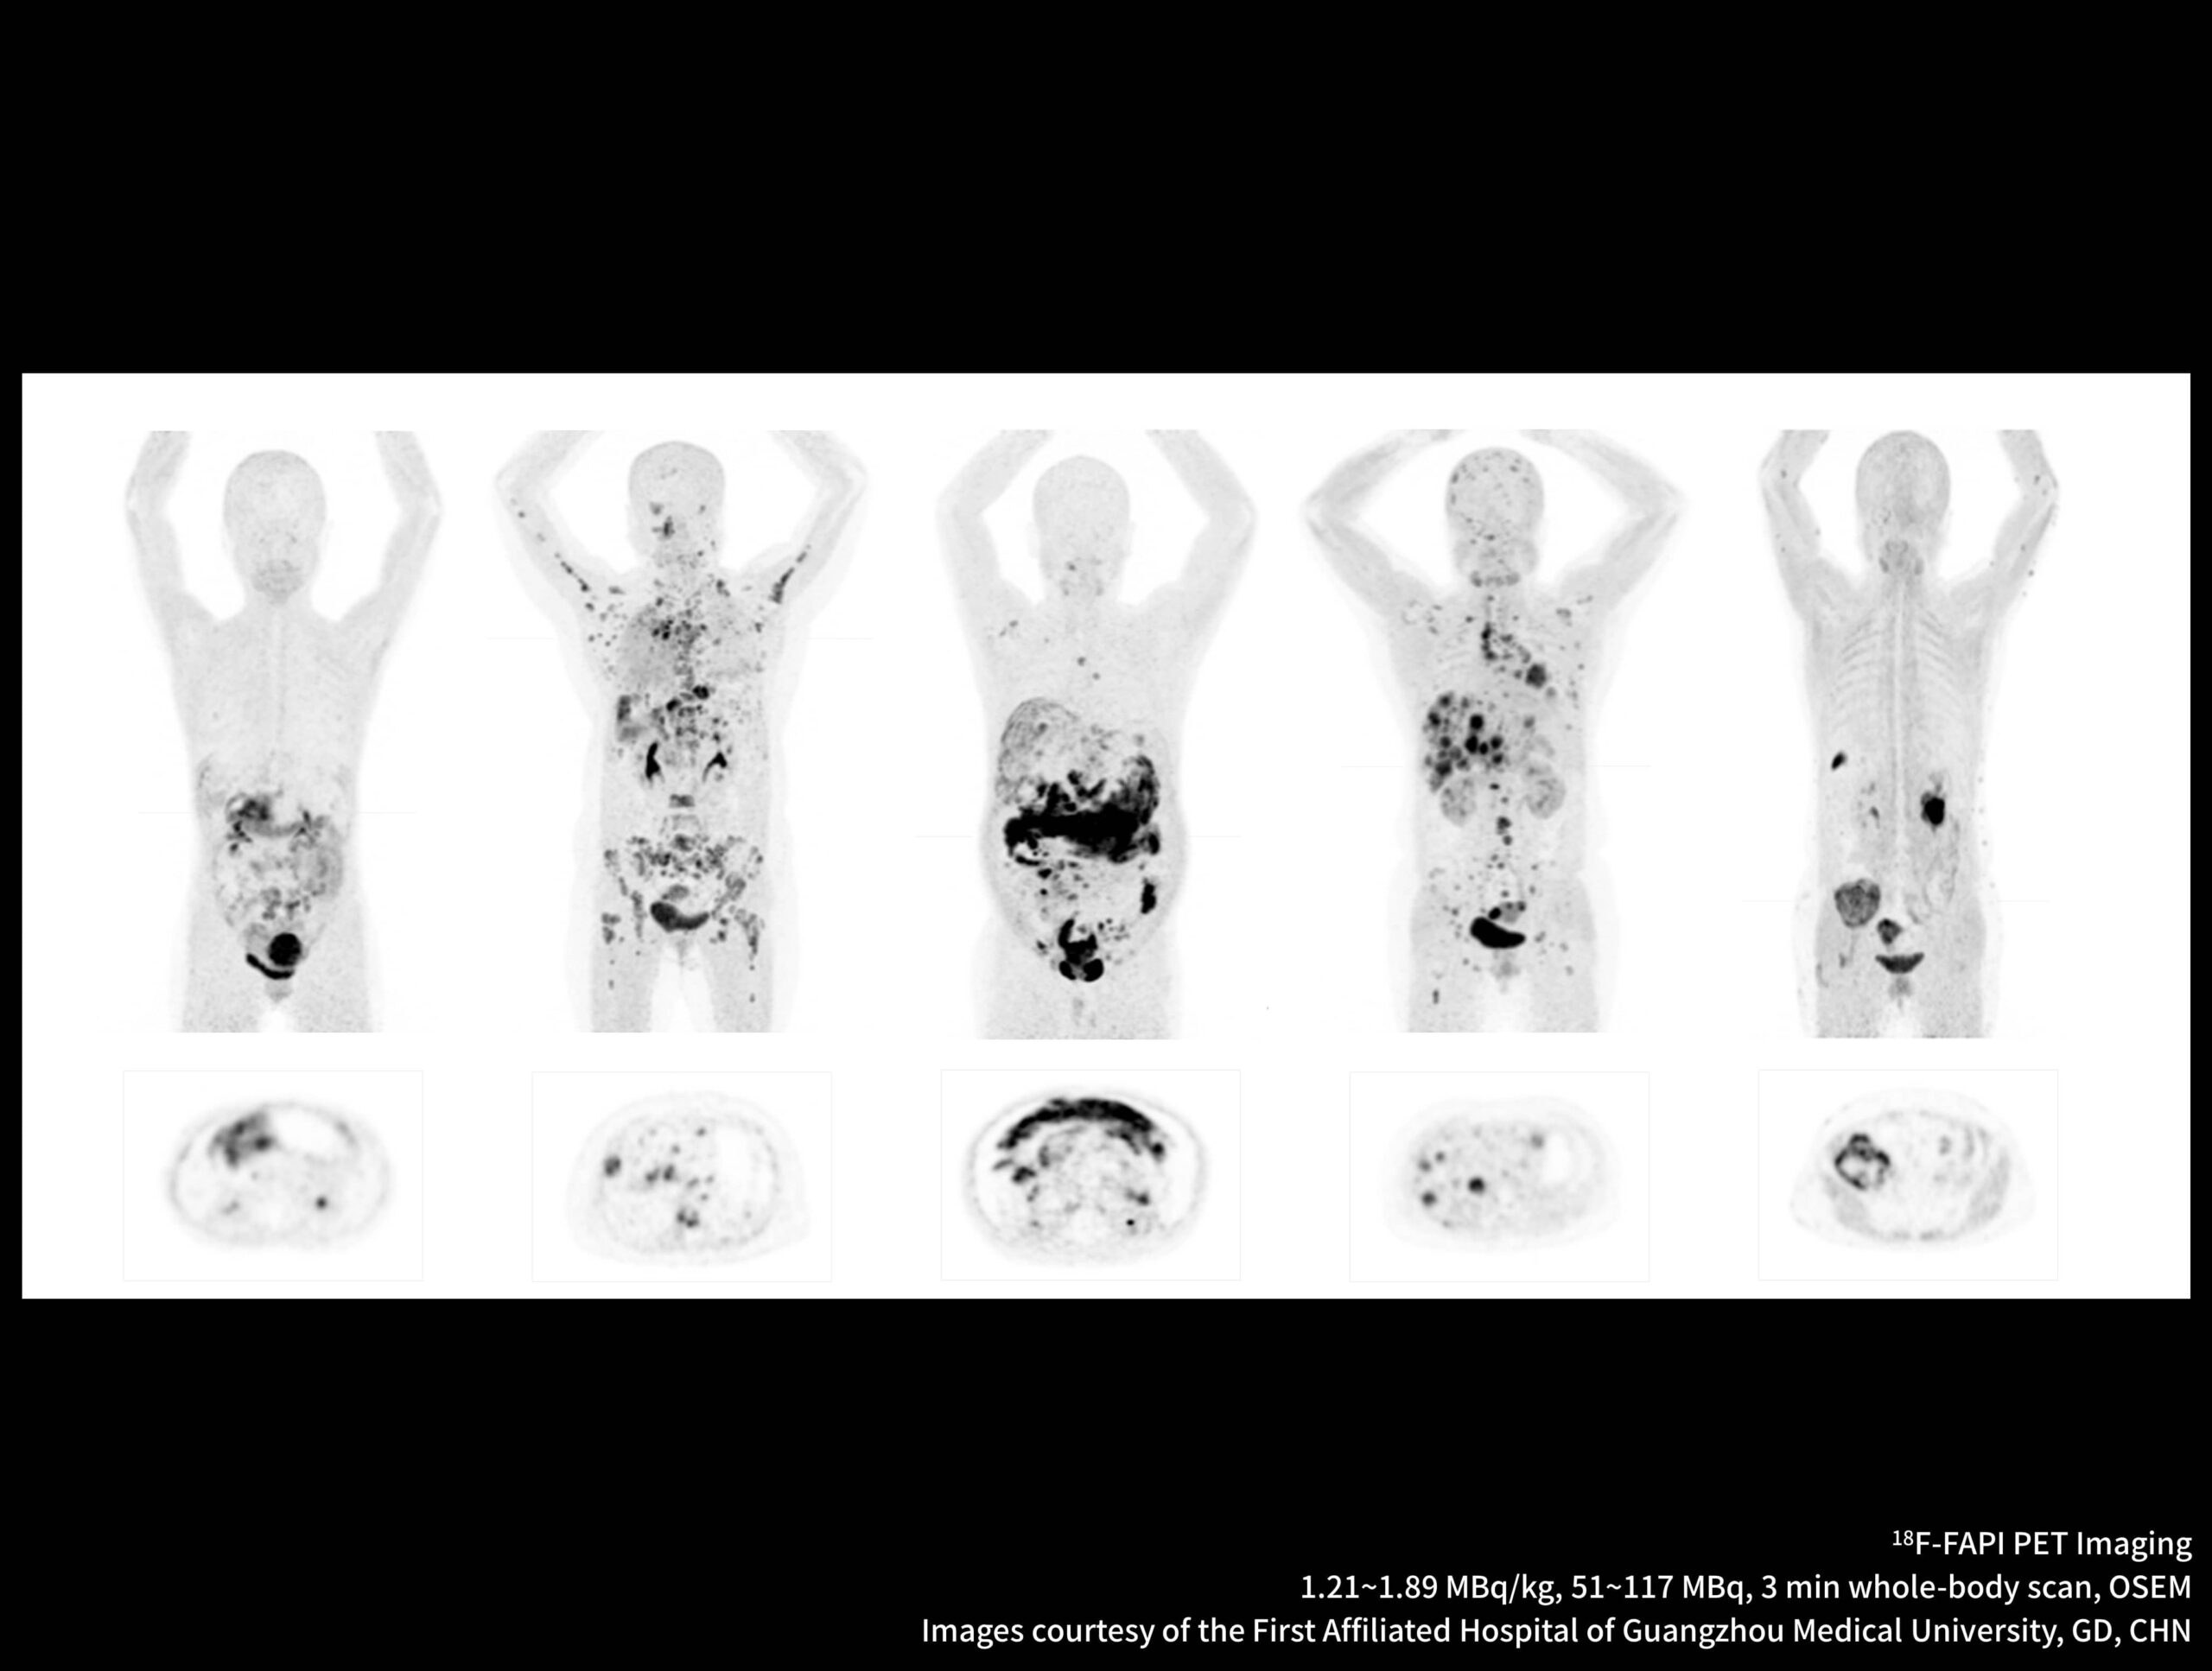

Imagistică PET/CT cu noi radiotrasori

Galerie de cazuri uMI Panorama

Metastazele extinse ale cancerului de sân sunt dezvăluite clar de sistemul high-resolution cu TOF ultra-rapid